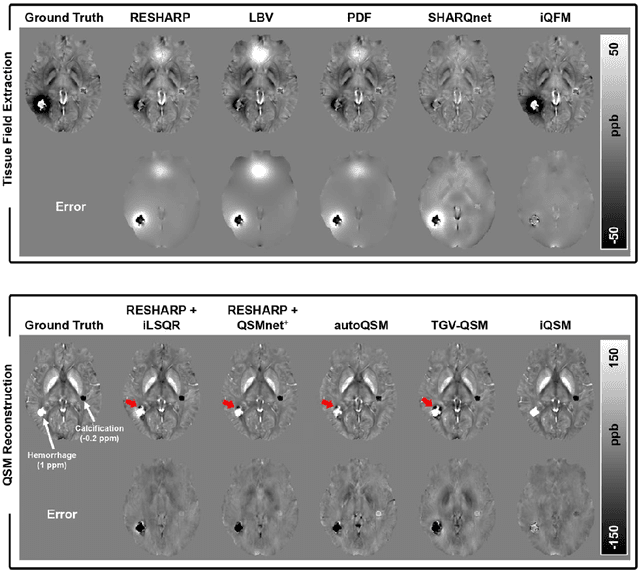

Abstract:Quantitative susceptibility mapping (QSM) is a valuable MRI post-processing technique that quantifies the magnetic susceptibility of body tissue from phase data. However, the traditional QSM reconstruction pipeline involves multiple non-trivial steps, including phase unwrapping, background field removal, and dipole inversion. These intermediate steps not only increase the reconstruction time but amplify noise and errors. This study develops a large-stencil Laplacian preprocessed deep learning-based neural network for near instant quantitative field and susceptibility mapping (i.e., iQFM and iQSM) from raw MR phase data. The proposed iQFM and iQSM methods were compared with established reconstruction pipelines on simulated and in vivo datasets. In addition, experiments on patients with intracranial hemorrhage and multiple sclerosis were also performed to test the generalization of the novel neural networks. The proposed iQFM and iQSM methods yielded comparable results to multi-step methods in healthy subjects while dramatically improving reconstruction accuracies on intracranial hemorrhages with large susceptibilities. The reconstruction time was also substantially shortened from minutes using multi-step methods to only 30 milliseconds using the trained iQFM and iQSM neural networks.